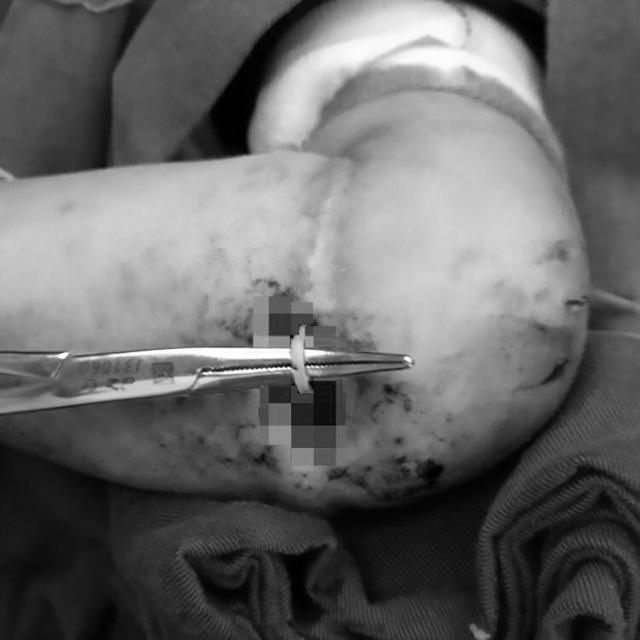

Các bác sĩ đã phẫu thuật và lấy ra chiếc dây thun bị "ăn sâu" vào cánh tay.

Rất may, Le Le đã được phẫu thuật kịp thời. Bé gái hiện vẫn nằm tại bệnh viện nhi và đang trên đà hồi phục.